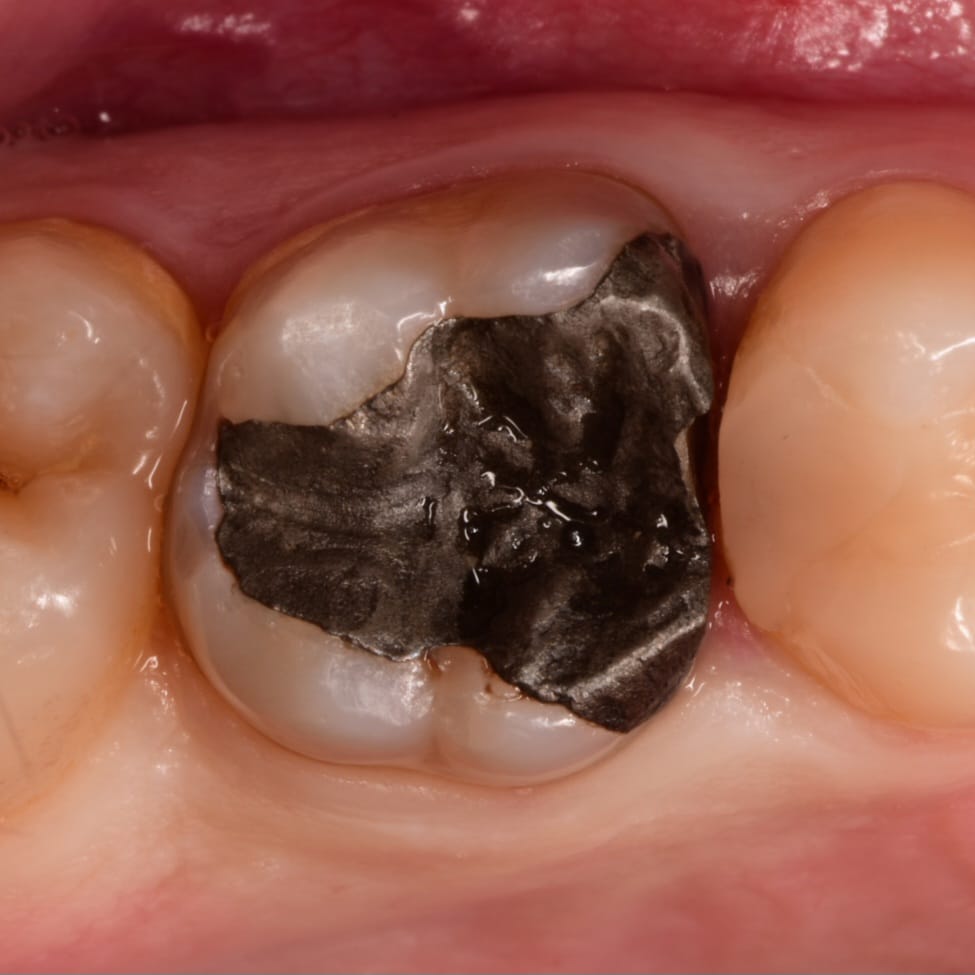

Initial situation showing large amalgam filling with open contact , the patient said that he replaced it for more than 2 times and the problem of food impaction still

Amalgam removal

Clean cavity ready for D.M.E

All caries removed by using CDD